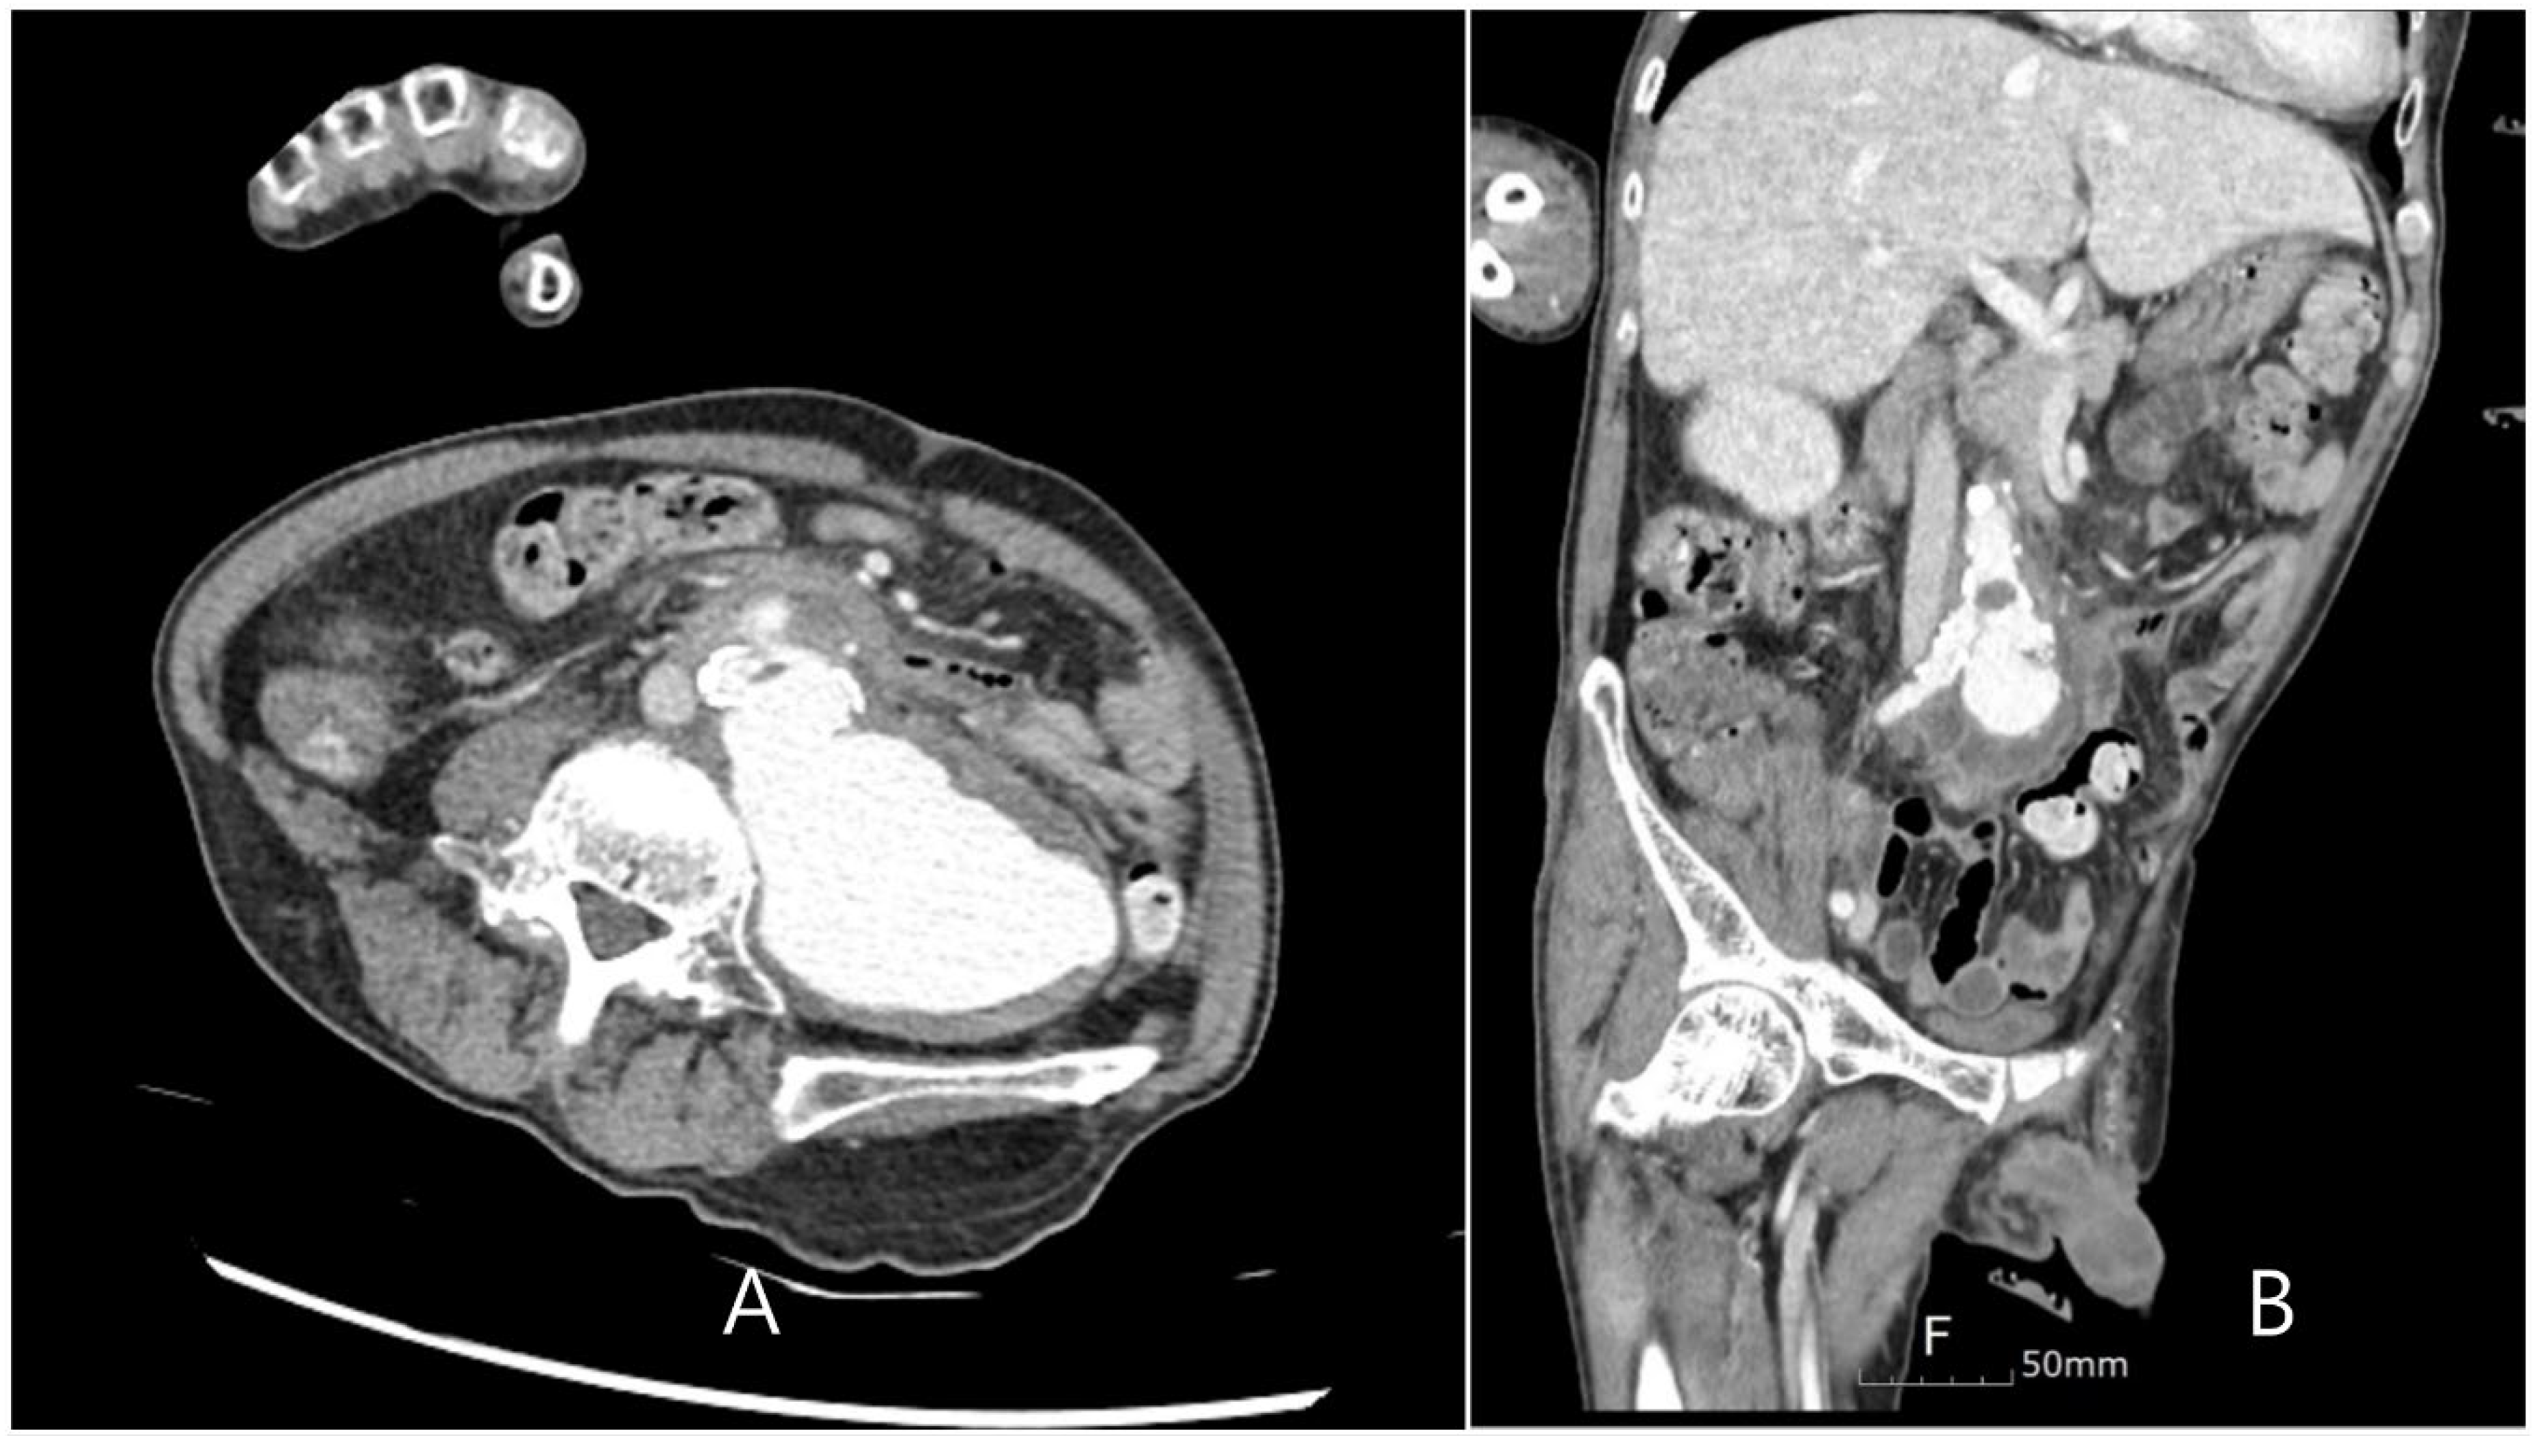

A 63-year-old-male presented to the emergency room with a fever of unknown origin that had not responded to antibiotic treatment for two weeks. In the nursing hospital, pneumonia and urinary tract infections, which commonly occur in hospitalized patients, were excluded during the examination, and the patient was diagnosed as having an unknown fever. A combination of 4.5 g of Piperaciilin and tazobactam was administered intravenously every 6 hours as a broad-spectrum antibiotic. The patient had been bedridden due to a traumatic subdural hemorrhage and a left corona radiata infarction. The patient also suffered a myocardial infarction that required aspirin administration. In the emergency room, the patient had no pain or tenderness in the body, and the lung sound was clear. The patient presented with mild leukocytosis, elevated C-reactive protein levels, and an elevated erythrocyte sedimentation rate. Rheumatoid diseases were excluded because of low complement levels, low immune antibody levels, and the absence of any related symptoms when examined by a rheumatologist. Five days after admission to the infection department, Candida albicans was cultured from the blood, and fluconazole was administered. Despite the administration of antifungal agents and antibiotics, a spiking fever of more than 40°C, occurring 2–3 times a day, persisted. Echocardiography was performed to determine the cause of the fever and to rule out infective endocarditis. A cardiologist performed transthoracic echocardiography; however, no vegetation was observed. The following day, transesophageal echocardiography was performed; however, vegetation was still not observed. After receiving conservative treatment for two weeks, the patient suddenly complained of pain in the right arm and localized swelling on the antecubital fossa during the third week of hospitalization. The pain was not accompanied by hyperemia or skin redness, but a tender, rigid, fixed, and palpable pulsatile mass was observed. Computed tomography (CT) of the upper limb was performed, revealing an aneurysm of the right brachial artery (Figure 1). Vascular ultrasonography revealed that the aneurysm contained a thrombus at the brachial bifurcation. Its maximum diameter was approximately 2.3 cm. The septic focus was determined to be a mycotic aneurysm of the brachial artery, and emergency surgery was performed. The mycotic aneurysm was completely removed, and bypass surgery was performed from the brachial artery to the radial and ulnar arteries using a bovine patch.

Figure 1. A, B: Brachial artery mycotic aneurysm is observed in upper extremity CT. C: Thrombosis and cellulitis around aneurysm are examined in Doppler.